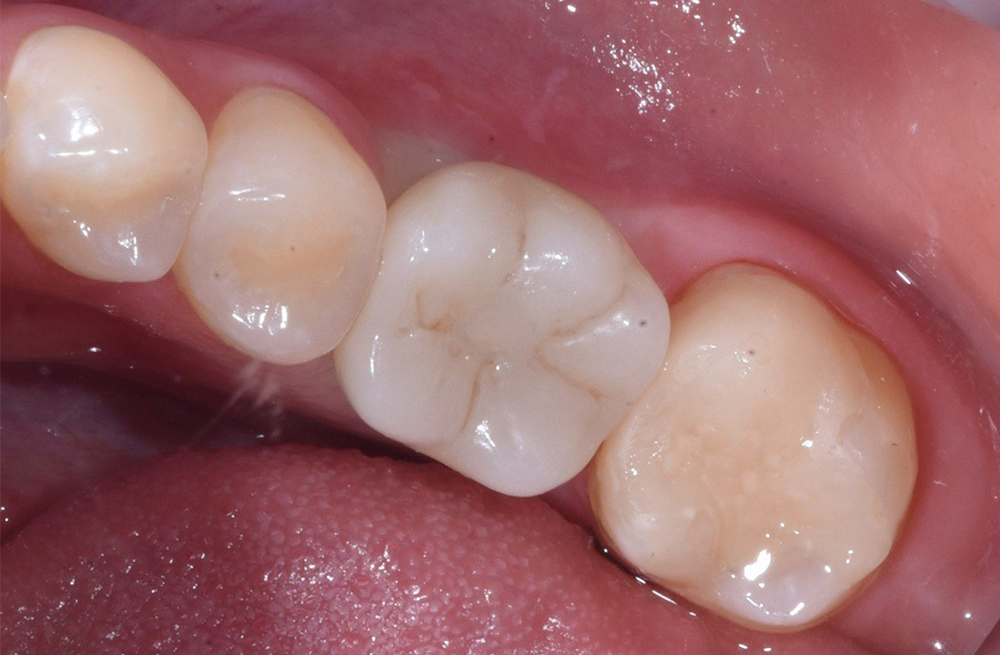

Восстановление жевательной группы зубов швейцарским имплантатом и цельнокерамической реставрацией